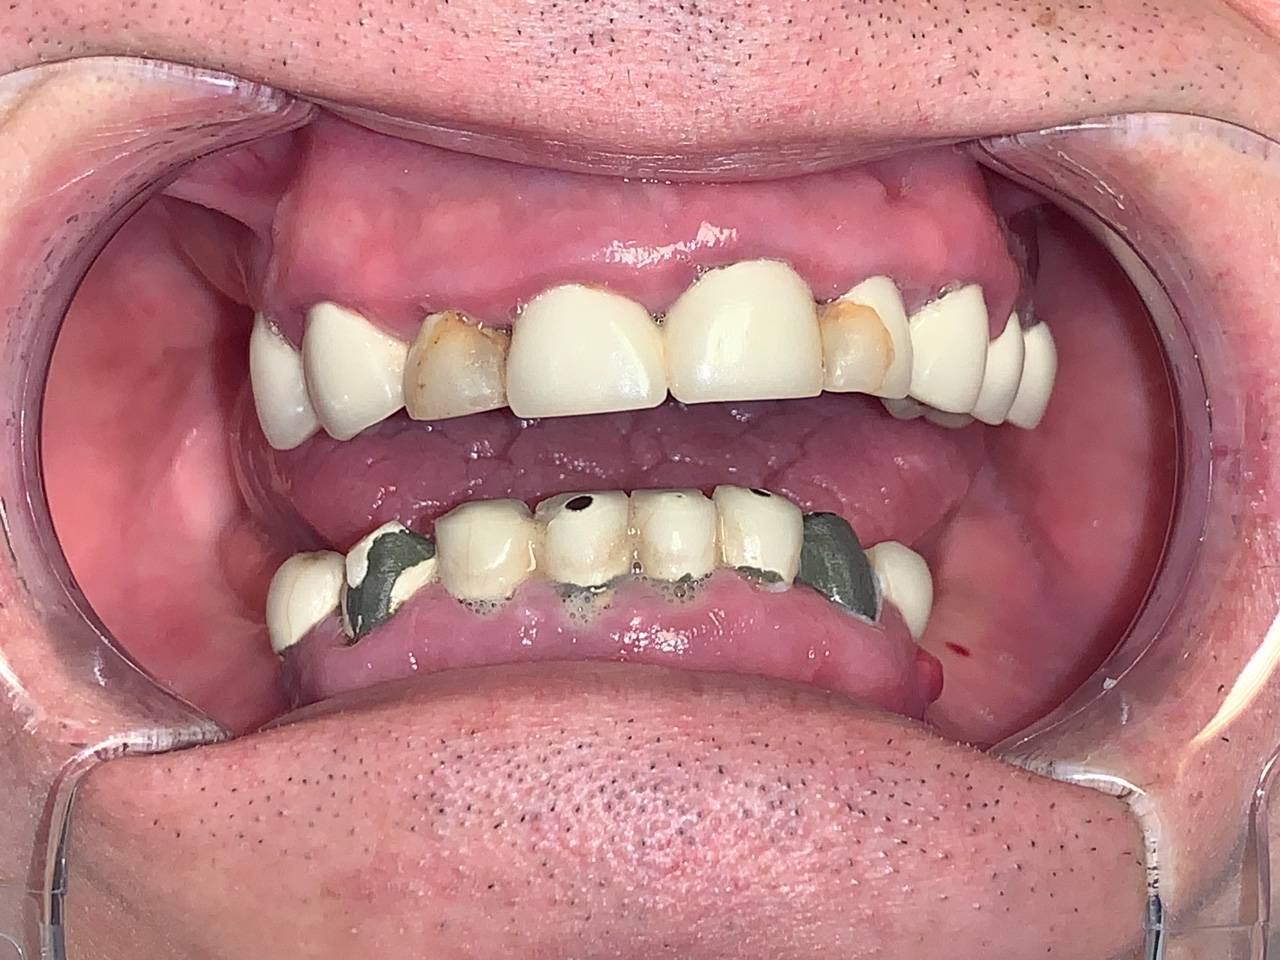

Foghiányos, fertőző gyökerekkel teli szájüreg helyreállítása

Foghiányos, fertőző gyökerekkel teli szájüreg helyreállítása esztétikailag és funkcionálisan 9 nap alatt.

A rossz fogakat és gyökereket eltávolítottuk, és azonnal terhelhető IHDE svájci implantátumokkal pótoltuk.

Az esztétikus koronák cirkóniumból készültek, hogy természetesebb hatást érjünk el